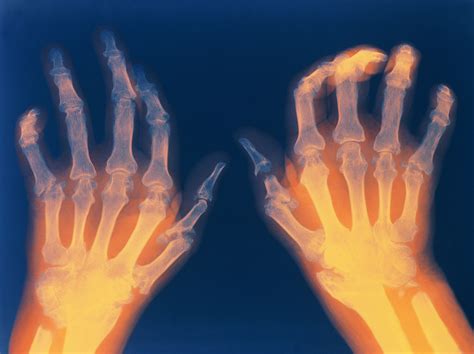

Hand with Rheumatoid Arthritis Stock Vector - Illustration of anatomy

Hand Braces For Arthritis